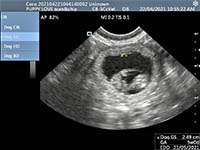

Mobile Ultrasound Pregnancy Scanning and Microchipping Services

Puppy Love scan and chip